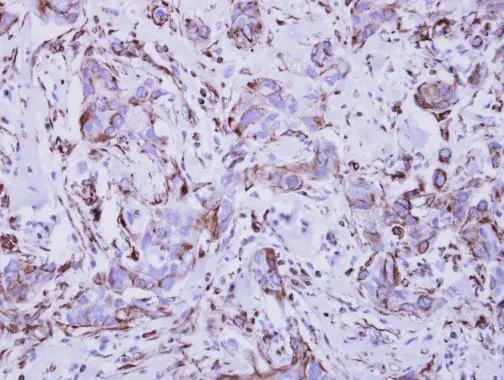

Anti-Interferon gamma Receptor 1 antibody used in IHC (Paraffin sections) (IHC-P). GTX103098

GTX103098 IHC-P Image

Immunohistochemical analysis of paraffin-embedded human breast cancer, using Interferon gamma Receptor 1(GTX103098) antibody at 1:250 dilution.

Antigen Retrieval: Trilogy™ (EDTA based, pH 8.0) buffer, 15min